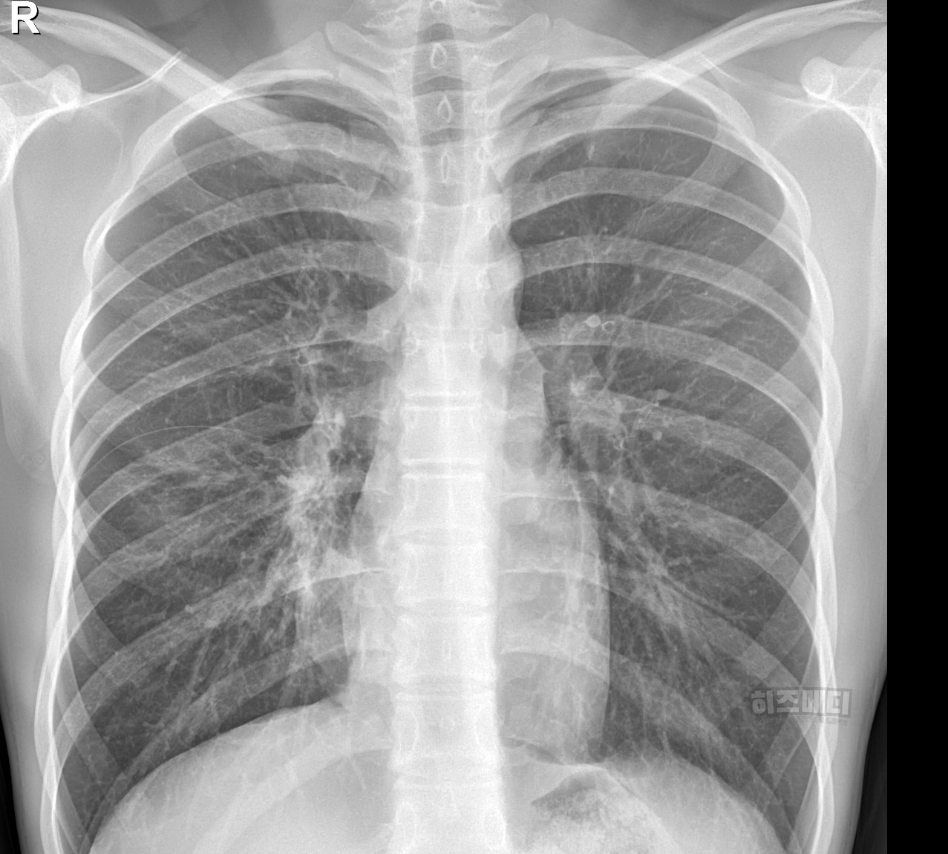

1) 흉부 엑스레이 촬영

폐에 염증이 있는지 확인할 때 흉부 엑스레이를 시행할 수 있습니다. 보통 폐렴으로 발전한 경우, 흉부 엑스레이에서 폐에 하얀 음영이 나타납니다.

마이코플라스마 폐렴은 일반적으로 폐렴의 전형적인 엑스레이 소견과는 다를 때가 많습니다. 폐의 폐포와 혈관사이를 간질이라고 부르는데, 이 부분에 주로 하얀 음영들이 많이 보이게 됩니다.

또한 병변이 양쪽 폐에서 동시에 관찰되는 경우가 종종 나타나며 주로 폐의 하엽에 많이 나타납니다. 미세한 결절이나 그물망 같은 모습으로 나타나기도 합니다.

마이코플라스마 폐렴은 엑스레이 사진에서는 병변이 심하지 않은데도 증상을 심하게 호소하는 경우가 있으며, 반대로 엑스레이 소견은 심해 보이는데 증상은 경미한 경우도 흔합니다. 따라서 마이코플라스마 감염을 확진하기 위해서는 임상 증상과 혈액검사 등의 종합적인 평가가 필요합니다.